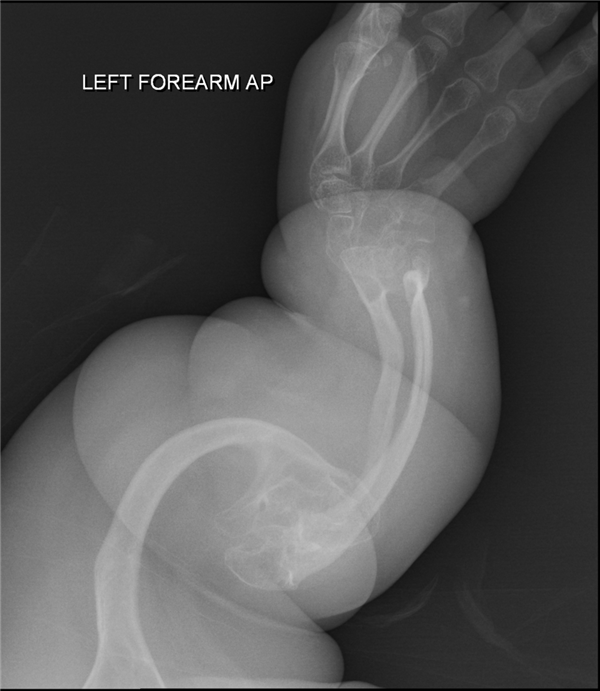

其他患者X光片——严重骨折

当时,医生就给孩子拍摄了髋关节部位的X光片,结果在影像资料里发现了2处骨折,且处于不同的愈合阶段,说明2次骨折不是同一时间发生的。

接着医生又给孩子做了全身检查,在其他身体部位,又又又发现2处骨折,然后事态就升级了。

成骨不全症,也就是我们常说的瓷娃娃病,也称之为脆骨病,是一种罕见遗传疾病,发病率约为1/15000-1/20000。

典型特征就是骨头脆弱,微小的外力就能导致骨折,比如打个喷嚏、翻个身、伸手够东西,成年后骨折情况会相对少一些。